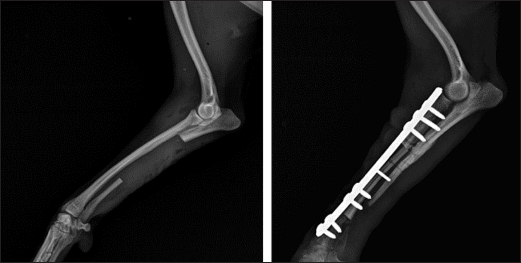

Fig. 4. Mediolateral and craniocaudal radiographs of antebrachial bones, 9 weeks after the revision surgery showing very good cortical graft bridging.

Fig. 5. Left—mediolateral radiograph of antebrachial bones 12 weeks after the revision surgery after the removal of screws from the cortical autograft; Right—mediolateral radiograph by the 15th week demonstrating complete union of the radial fracture and bone callus remodeling.

During the control examination by the 9th post-operative week, the weight bearing with the limb was steady, whereas lameness, pain, and swelling were absent. Radiologically, an excellent bridging of the cortical graft without loosening of fixation implants was demonstrated (Fig. 4).

After the second control examination by the 12th post-operative week, because of the good radiological and clinical outcome, the three screws in the cortical graft were removed, leaving only screws in the proximal and distal bone fragments. By the 15th week, due to excellent clinical outcomes, all implants were removed (Fig. 5).